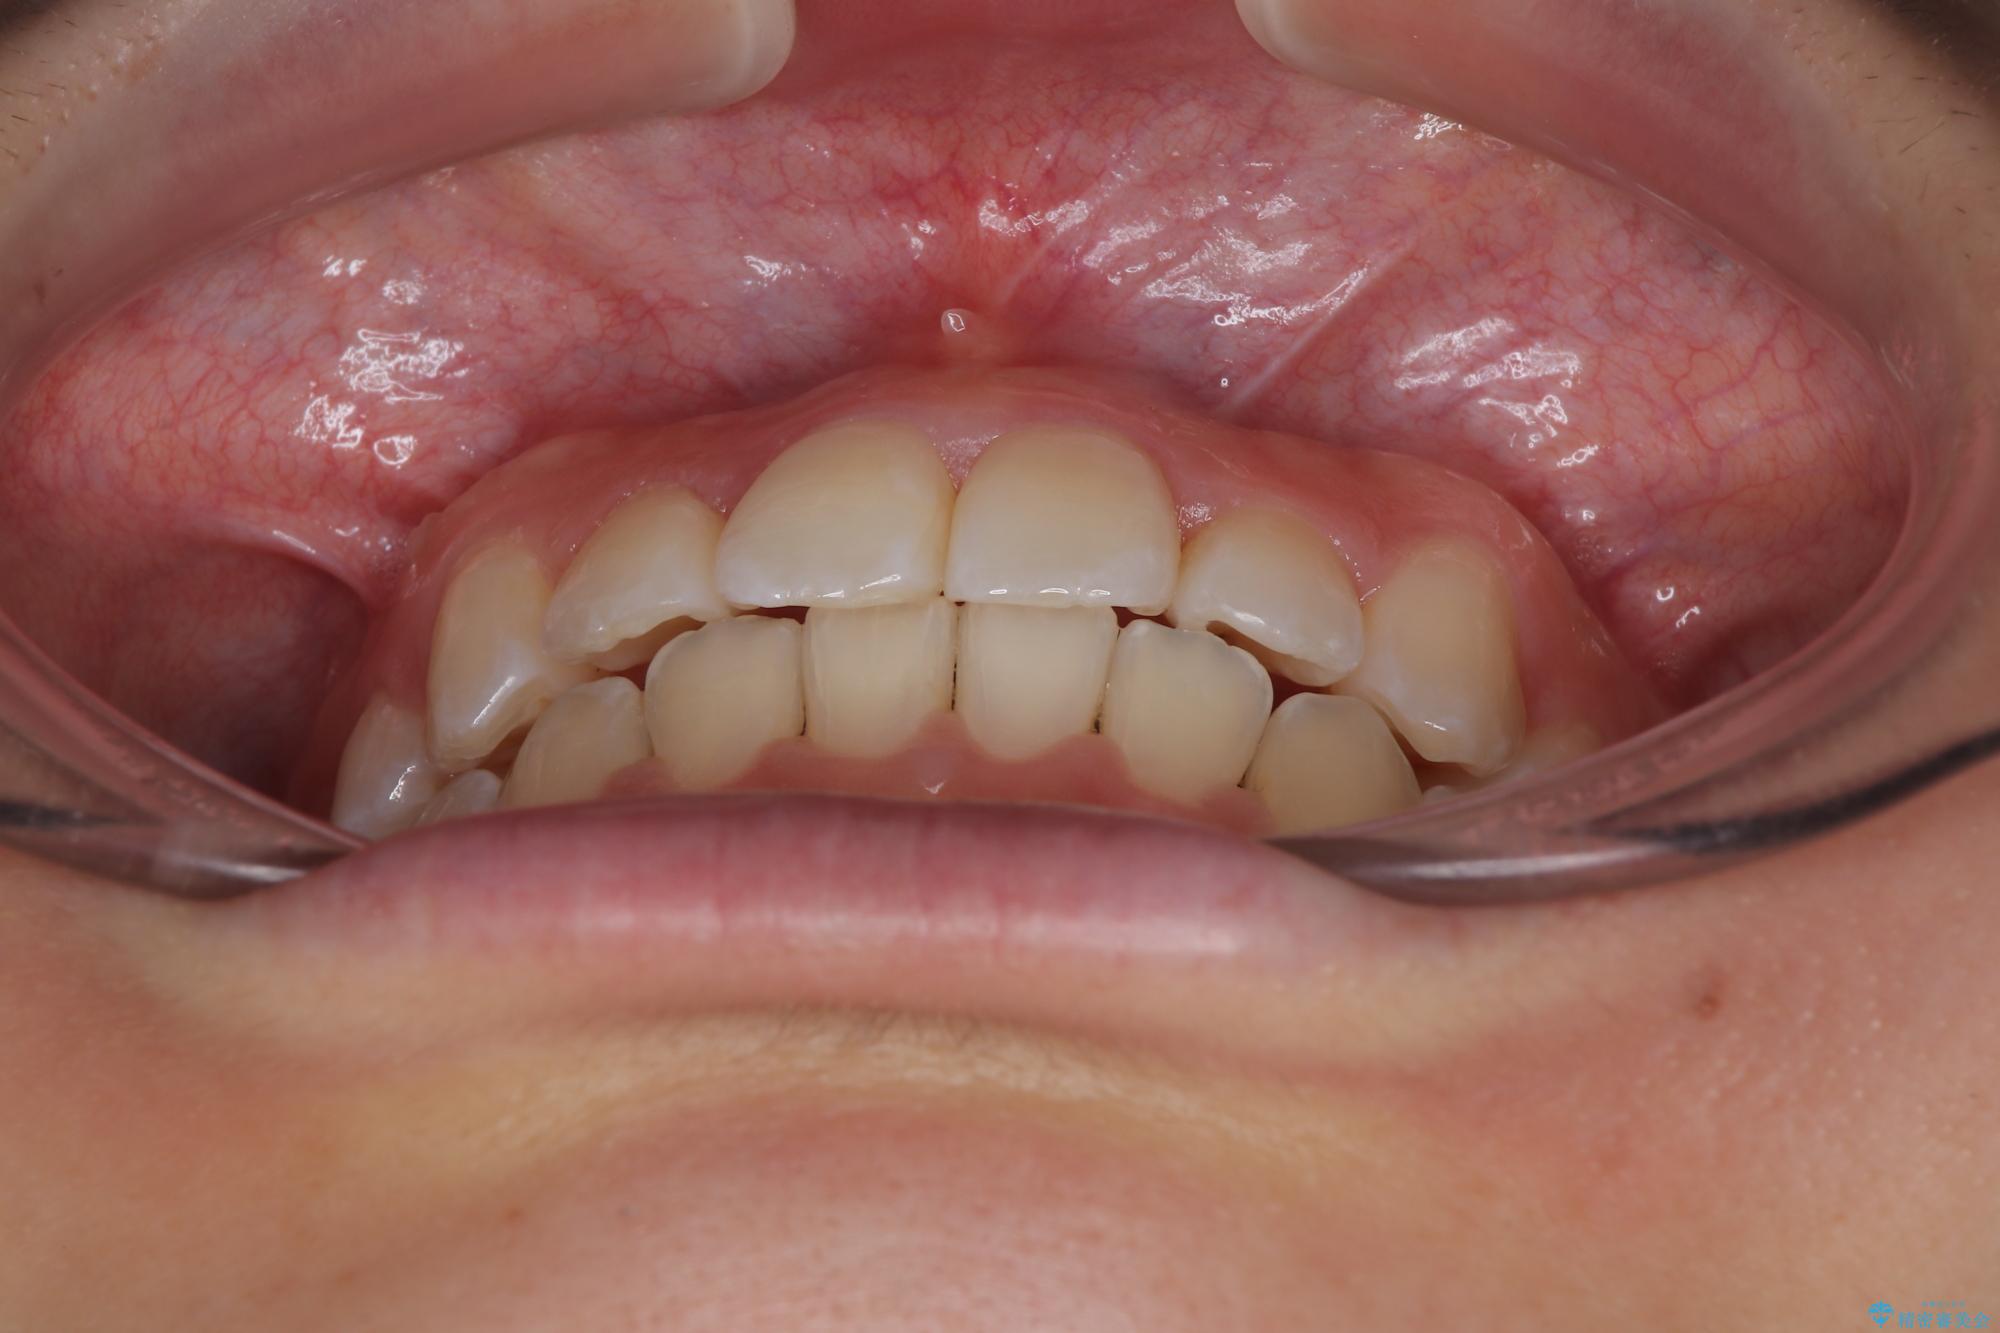

- 上顎前歯のクロスバイトを気にして来院された患者様です。

装置の外見を気にしていましたが、短期間で治療を終えることができるだろうと伝えると、安価であるメタルブラケットを選択されました。

想定通り、1年強で綺麗に仕上げることができました。